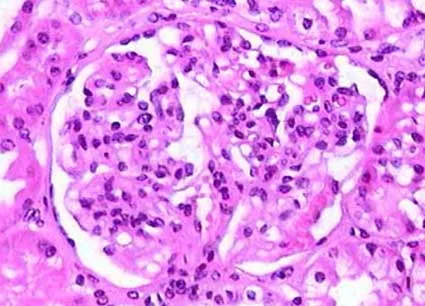

Doação renal em mulheres jovens pode impactar mais o feto do que a mãe — e esse dado muda o pré-operatório. O maior estudo já feito mostra aumento de PIG e sinais de disfunção placentária silenciosa, especialmente em nulíparas. Se você ainda não discute isso de forma explícita no consentimento, talvez esteja subestimando o risco.